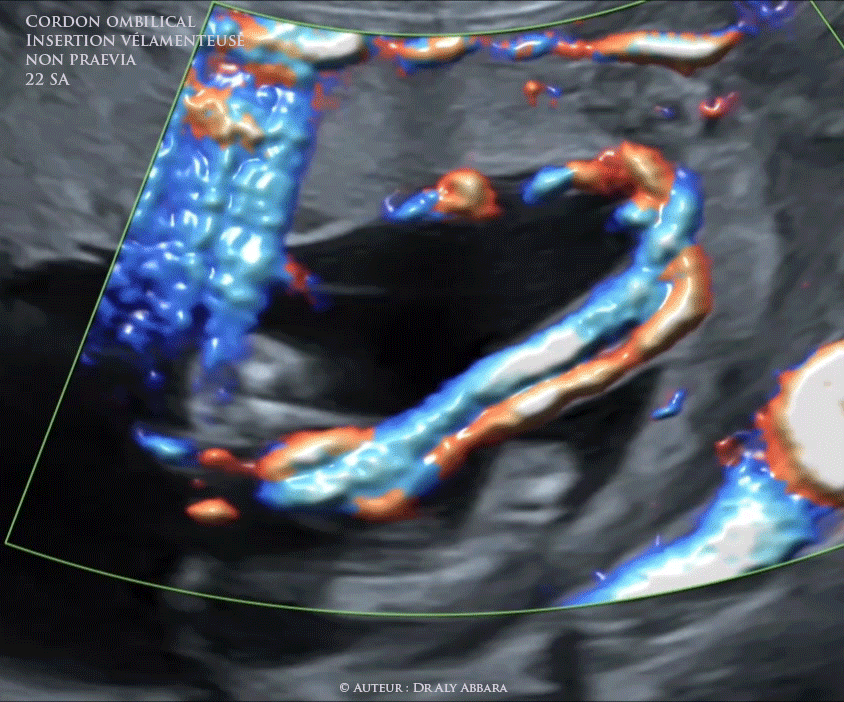

Insertion vélamenteuse (en parapluie) du cordon ombilical - grossesse de 22 SA

• Vidéo échographique montrant une insertion vélamentesue du condon ombilical - placenta d'insertion fundique.

• Il s'agit d'une insertion vélamenteuse du cordon à proximité du bord latéral du placenta (à plus de 2 cm du bord placentaire) et à distance du pôle inférieur de la cavité utérine (pas de vasa prævia).

• Grossesse de 22 SA